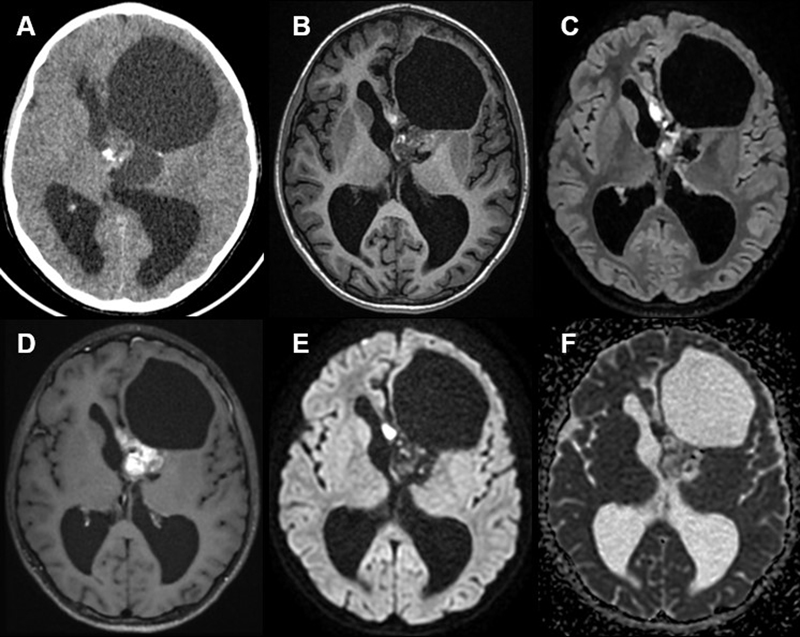

A 10-year-old boy presented with intracranial hypertension, found to be caused by a supratentorial (ST) intraventricular neoplasm. Magnetic resonance imaging (MRI) revealed a large mass within the left lateral ventricle having solid and cystic content (MRI performed after cyst aspiration) (Figure 1B–F). Computerized tomography (CT) showed the solid component to have intermediate density and calcification (Figure 1A), intense contrast enhancement (Figure 1D), and no diffusion restriction (Figure 1E). The tumor was subtotally resected. Morphologically, this tumor was mainly well-circumscribed from the brain parenchyma (with few infiltrating isolated cells around the periphery of the tumor). Pseudorosettes, microcysts and calcifications were observed (Figure 2A–B). There was no necrosis or microvascular proliferation, but the tumor presented a high mitotic count (6 mitoses per 5 high-power fields representing 1.6 mm2) and proliferation index (10 %). Immunohistochemistry (IHC) confirmed the preserved expression of H3K27me3, INI1 and ATRX. There was no immunopositivity for GFAP, OLIG2 or MN1, and the expression of EMA was cytoplasmic without dot-like or microlumen staining. NeuN and neurofilament were expressed by a subset of tumor cells, and nuclear translocation of β-catenin was present. There was a weak, but diffuse, immunoreactivity for BCOR (Figure 2C) and a focal positivity for SATB2 (Figure 2D). RNA sequencing evidenced a KDM2A::YAP1 gene fusion (Figure 2E). Next-generation sequencing failed to reveal any other alteration. The tumor was not classifiable using the Heidelberg Brain Tumor and sarcoma (v12.8) or Bethesda Classifiers, nor by t-Distributed Stochastic Neighbor Embedding (t-SNE) or Uniform Manifold Approximation and Projection (UMAP) analyses (supplementary Figure 1), which included HGNET-BCOR and sarcomas with BCOR alterations and CNS and soft tissue tumors with YWHAE:NUTM2 or KDM2B fusions from our in-house database and previously reported (5). Forty-two months later, the patient presented a local recurrence of the tumor and a second surgery was performed. The recurrence histopathology was identical to the initial resection. The patient is alive without residue 60 months after the initial diagnosis and without any adjuvant treatment.

Figure 1: Radiological features

Axial unenhanced CT(A), T1-weighted (B), FLAIR (C), post-contrast T1-weighted (D), diffusion (E), and apparent diffusion coefficient (ADC) map (F) images of the patient, showing a large mass within the left lateral ventricle having solid and cystic content (MRI performed after cyst aspiration). CT showed the solid component to have intermediate density and calcification, intense contrast enhancement, and no diffusion restriction.